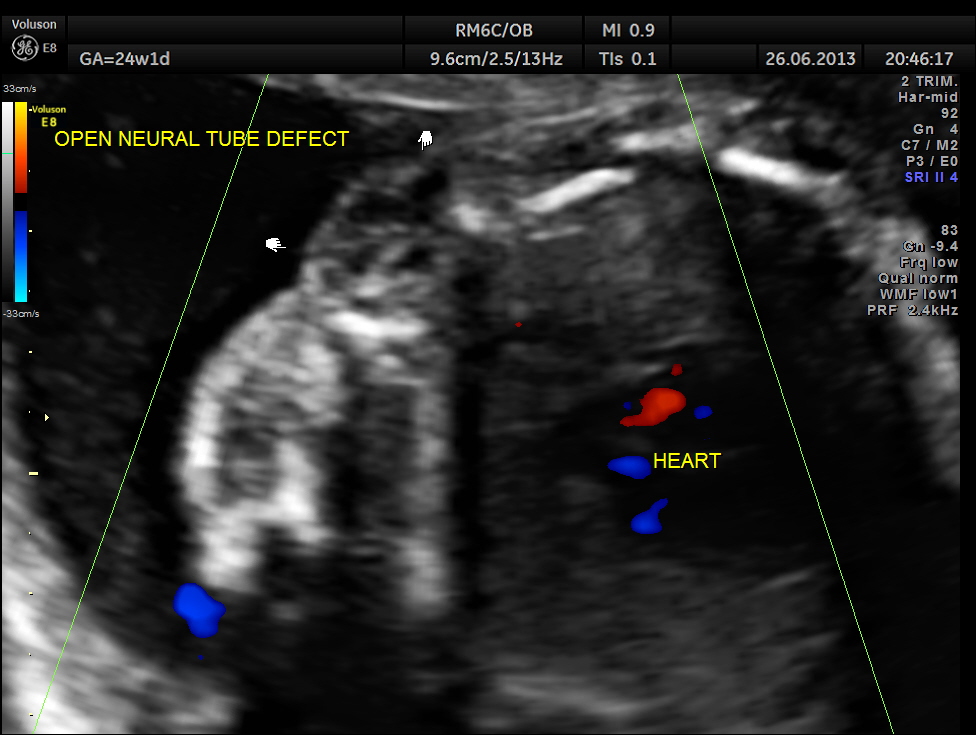

the following image shows the open neural tube defect at the same level as the heart.